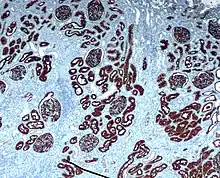

Neprilysin is expressed in a wide variety of tissues and is particularly abundant in kidney. It is also a common acute lymphocytic leukemia antigen that is an important cell surface marker in the diagnosis of human acute lymphocytic leukemia (ALL). This protein is present on leukemic cells of pre-B phenotype, which represent 85% of cases of ALL.[5]

Hematopoietic progenitors expressing CD10 are considered "common lymphoid progenitors", which means they can differentiate into T, B or natural killer cells.[6] CD10 is of use in hematological diagnosis since it is expressed by early B, pro-B and pre-B lymphocytes, and by lymph node germinal centers.[7] Hematologic diseases in which it is positive include ALL, angioimmunoblastic T cell lymphoma, Burkitt lymphoma, chronic myelogenous leukemia in blast crisis (90%), diffuse large B-cell lymphoma (variable), follicular center cells (70%), hairy cell leukemia (10%), and myeloma (some). It tends to be negative in acute myeloid leukemia, chronic lymphocytic leukemia, mantle cell lymphoma, and marginal zone lymphoma. CD10 is found on non-T ALL cells, which derive from pre-B lymphocytes, and in germinal center-related non-Hodgkin lymphoma such as Burkitt lymphoma and follicular lymphoma, but not on leukemia cells or lymphomas, which originate in more mature B cells.[8]

CD10 is used in clinical pathology for diagnostic purpose.

In lymphomas and leukemias

- Acute lymphoblastic leukemia (ALL) cells are CD10+.

- Follicular lymphoma (follicle centre cell lymphoma) are CD10+.

- Burkitt Lymphoma cells are CD10+.

- CD10+ diffuse large B cell lymphoma (CD10+ DLBCL)[20]

- Angioimmunoblastic T cell lymphoma (AITL) are CD10+[25][26] and distinguishes AITL from other T cell lymphomas (CD10−)[27]

- Some benign T cells can be CD10+[28]